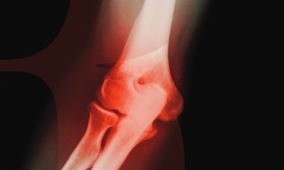

A Reumatológiai Expressz jelen száma is aktuális, a klinikai munkát támogató közleményekkel jelentkezik. Gyulladásos immunológiai kórképek gyakran járnak szemészeti érintettséggel, ezek megfelelő gondozása a szemész és a reumatológus közös feladata.